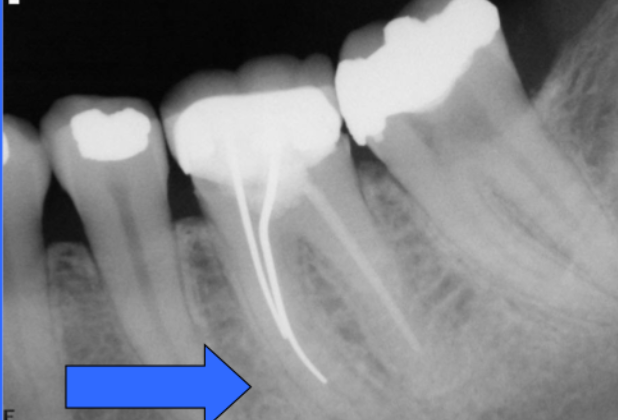

Q

what is this

A

endopot - all dirty files are placed on here